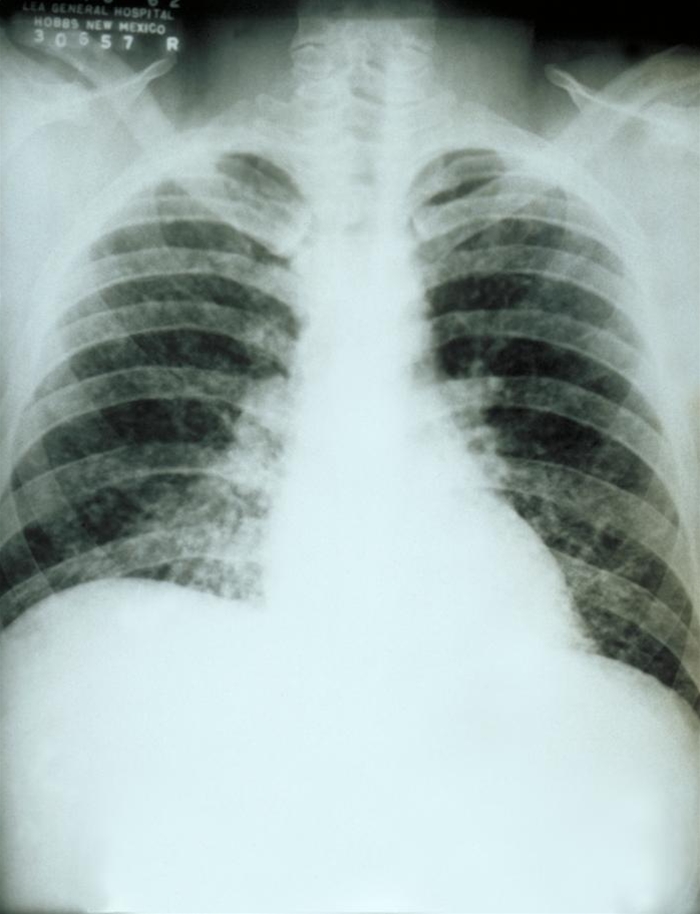

Histoplamose